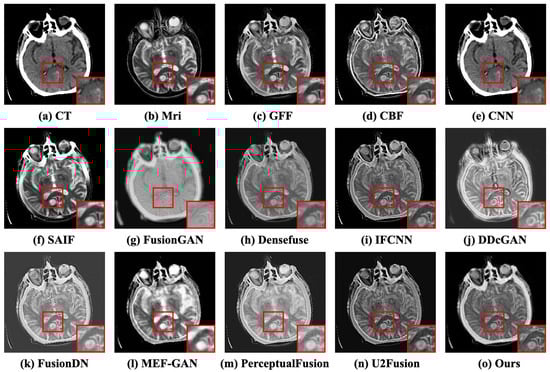

Case 2: Acute stroke presenting as right body weakness. This case is from a 45-year-old female with a sudden onset of right body weakness and trouble speaking ([Online]. Available: http://www.med.harvard.edu/aanlib/cases/case20/case.html, accessed on 15 May 2023). The subjective comparison results of the second case are depicted in Figure 8. These methods (e.g., GFF [10], SAIF [12], Densefuse [14], and IFCNN [15]) preserve some tissue texture information, but the fused images have lower contrast, resulting in missing cephalometric information. The comparison between CNN [13] and FusionGAN [35] has higher contrast, but the edges are blurred, and some information about brain tissue is lost. The MEF-GAN [36], U2Fusion [17], and PerceptualFusion [22] are unable to attain distinct textures or boundaries. The superior colliculus of the fused results in the red box (e.g., DDcGAN [21], FusionDN [16], and CFGAN) has higher brightness and richer details, but the bone information of DDcGAN [21] lacks details, including edges and texture. Our proposed method can reserve more significant information, particularly gradient information, contrast, boundary, and textural details. The objective comparison results are denoted in Table 2. It illustrates that the proposed CFGAN ranks first in SD, PSNR, SSIM, and MI. For the CC and VIF indicators, the CFGAN ranks third and second, respectively.

Figure 8.

The subjective comparison results of the second case. (a,b) represent the CT and MRI images. (c–n) denote the fused results of the competitors. (o) is the result of CFGAN.

Case 3: Multiple infarctions. The third case is a 55-year-old male who suffered multiple refractory focal seizures in the setting of pulmonary empyema ([Online]. Available: http://www.med.harvard.edu/aanlib/cases/case34/case.html, accessed on 15 May 2023). The fused results of the subjective comparison for the third case are illustrated in Figure 9. The source MRI has more clarity and more tissue detail than the CT image, and it makes sense for both of the above pieces of information to be retained in the fused image. Nevertheless, these methods (e.g., GFF [10], CBF [11], and FusionGAN [35]) have weak visual contrast. There are distortions in the contours of images (e.g., SAIF [12], DDcGAN [21], IFCNN [15], and MEF-GAN [36]). In general, SAIF [12], DDcGAN [21], and CFGAN achieve superior perceived quality. Viewing the atrium in the red box, we can observe that CBF [11], SAIF [12], IFCNN [15], DDcGAN [21], U2Fusion [17], and CFGAN reserve more texture details. The six objective evaluation indicators are presented in Table 3. The proposed method CFGAN is proved to show better performance compared to the other twelve methods.

Figure 9.

The subjective comparison results of the third case. (a,b) represent the CT and MRI images. (c–n) denote the fused results of the competitors. (o) is the result of CFGAN.

Case 4: Fatal stroke. The experimental case was collected from a patient who developed a sudden onset of left-sided hemiparesis, muteness, and bilateral ptosis ([Online]. Available: http://www.med.harvard.edu/aanlib/cases/case37/case.html, accessed on 15 May 2023). The cerebral infarct lesion showed abrupt contrast variation in both CT and MRI images as illustrated in Figure 10a,b. GFF [10], CBF [11], and SAIF [12] have inferior performance in retaining the profile information of the CT image. IFCNN [15], Densefuse [14], and U2Fusion [17] show lower contrasted images. MEF-GAN [36] and CFGAN preserve more cranial information from CT images and more tissue information from MRI images compared with U2Fusion [17]. Still, some illumination information is lost at the contour by MEF-GAN [36]. The objective comparison results are tabulated in Table 4. It demonstrates that the CFGAN performs best in the SD, PSNR, SSIM, VIF, and MI indicators.

Figure 10.

The subjective comparison results of the fourth case. (a,b) represent the CT and MRI images. (c–n) denote the fused results of the competitors. (o) is the result of CFGAN.